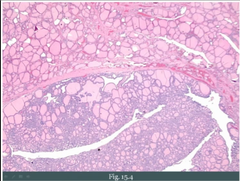

Serous/Mucinous Surface Epithelial Ovarian Tumors

Serous (watery, 80%) vs. mucinous (mucus, 20%) based on what fills the cyst Benign (cystadenoma): single cysts, flat lining, premenopausal vs. Malignant (cystadenocarcinoma): complex, thick/shaggy lining, postmenopausal vs. Borderline: between benign/malignant *BRCA1 mutation --> risk of serous carcinoma of the ovary and fallopian tubes